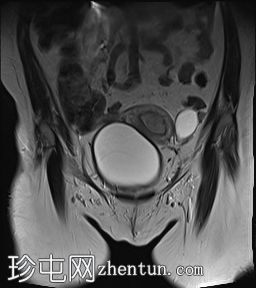

轴位

T2加权像

子宫体积增大,宫底可见息肉样病变,T2加权像呈异常中高信号强度。病变可见轻度扩散受限,增强后呈均匀强化。病变与宫底交界区之间可见一界限清晰的异常高T2信号区域,可能为囊性变性。未见病变超出交界区。

在剖宫产切口远端的前壁上,可见另一处类似的较小病灶。

左侧附件囊性病变,T1加权像信号异常低,T2加权像信号异常高。无增强扫描强化。

子宫内膜息肉是子宫内膜组织的结节状突起。通常表现为T2加权像信号异常高,增强扫描后呈均匀强化。

病理检查通常显示增生期子宫内膜紊乱。